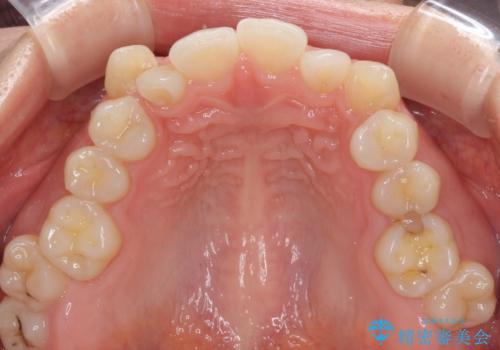

- 前歯のデコボコや八重歯、舌癖による開咬を気にして来院された患者様です。

目立たない装置を希望されたので、上顎が裏側装置のハーフリンガルを選択し、上顎小臼歯1本を抜歯して、補助装置を併用して矯正治療を行うこととしました。

補助装置を事前に使用したことで、あっという間に八重歯が改善し、ハーフリンガルにしては1年半もかからずに治療を終えることができました。